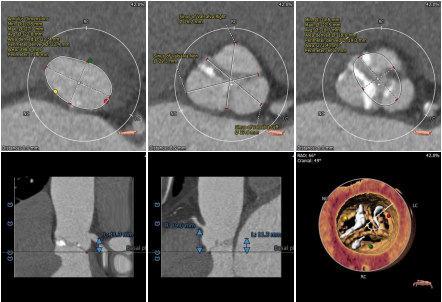

根部评估

Type1型二叶式主动脉瓣,L-N融合,主动脉瓣环周长83.8mm,平均周长径26.8mm。瓦式窦可。左冠开口高度16.3mm,右冠开口高度25.6mm。

主动脉弓部夹角略锐,角度84度,最短距离70.3mm,必要时可采取Snare辅助过弓;外周入路血管条件良好,无钙化,未发现其他血管病变,双侧入路血管管径可。

新疆自治区人民医院杨毅宁教授团队在手术前对患者进行整体评估讨论,考虑患者重度狭窄合并中度返流,解剖分型为Type1型二叶瓣,中度钙化。根据冠脉高度、瓣叶长度、瓦氏窦宽度分析冠脉风险较低,但BAV和瓣叶钙化易导致植入假体瓣膜形变、根部损伤及瓣周漏风险,因此手术需加以注意。

经充分讨论评估后决定,采用右侧股动脉为主入路,左侧辅助入路,二叶瓣跨瓣、球扩、释放工作体位选择双窦展开的最大角度RAO 13° CAU8°。22mm球囊预扩,预装AV26瓣膜,密切观察钙化及融合嵴推移情况。考虑二叶瓣和钙化对假体形态的影像,释放后双定位观察进一步确定人工瓣膜形态。